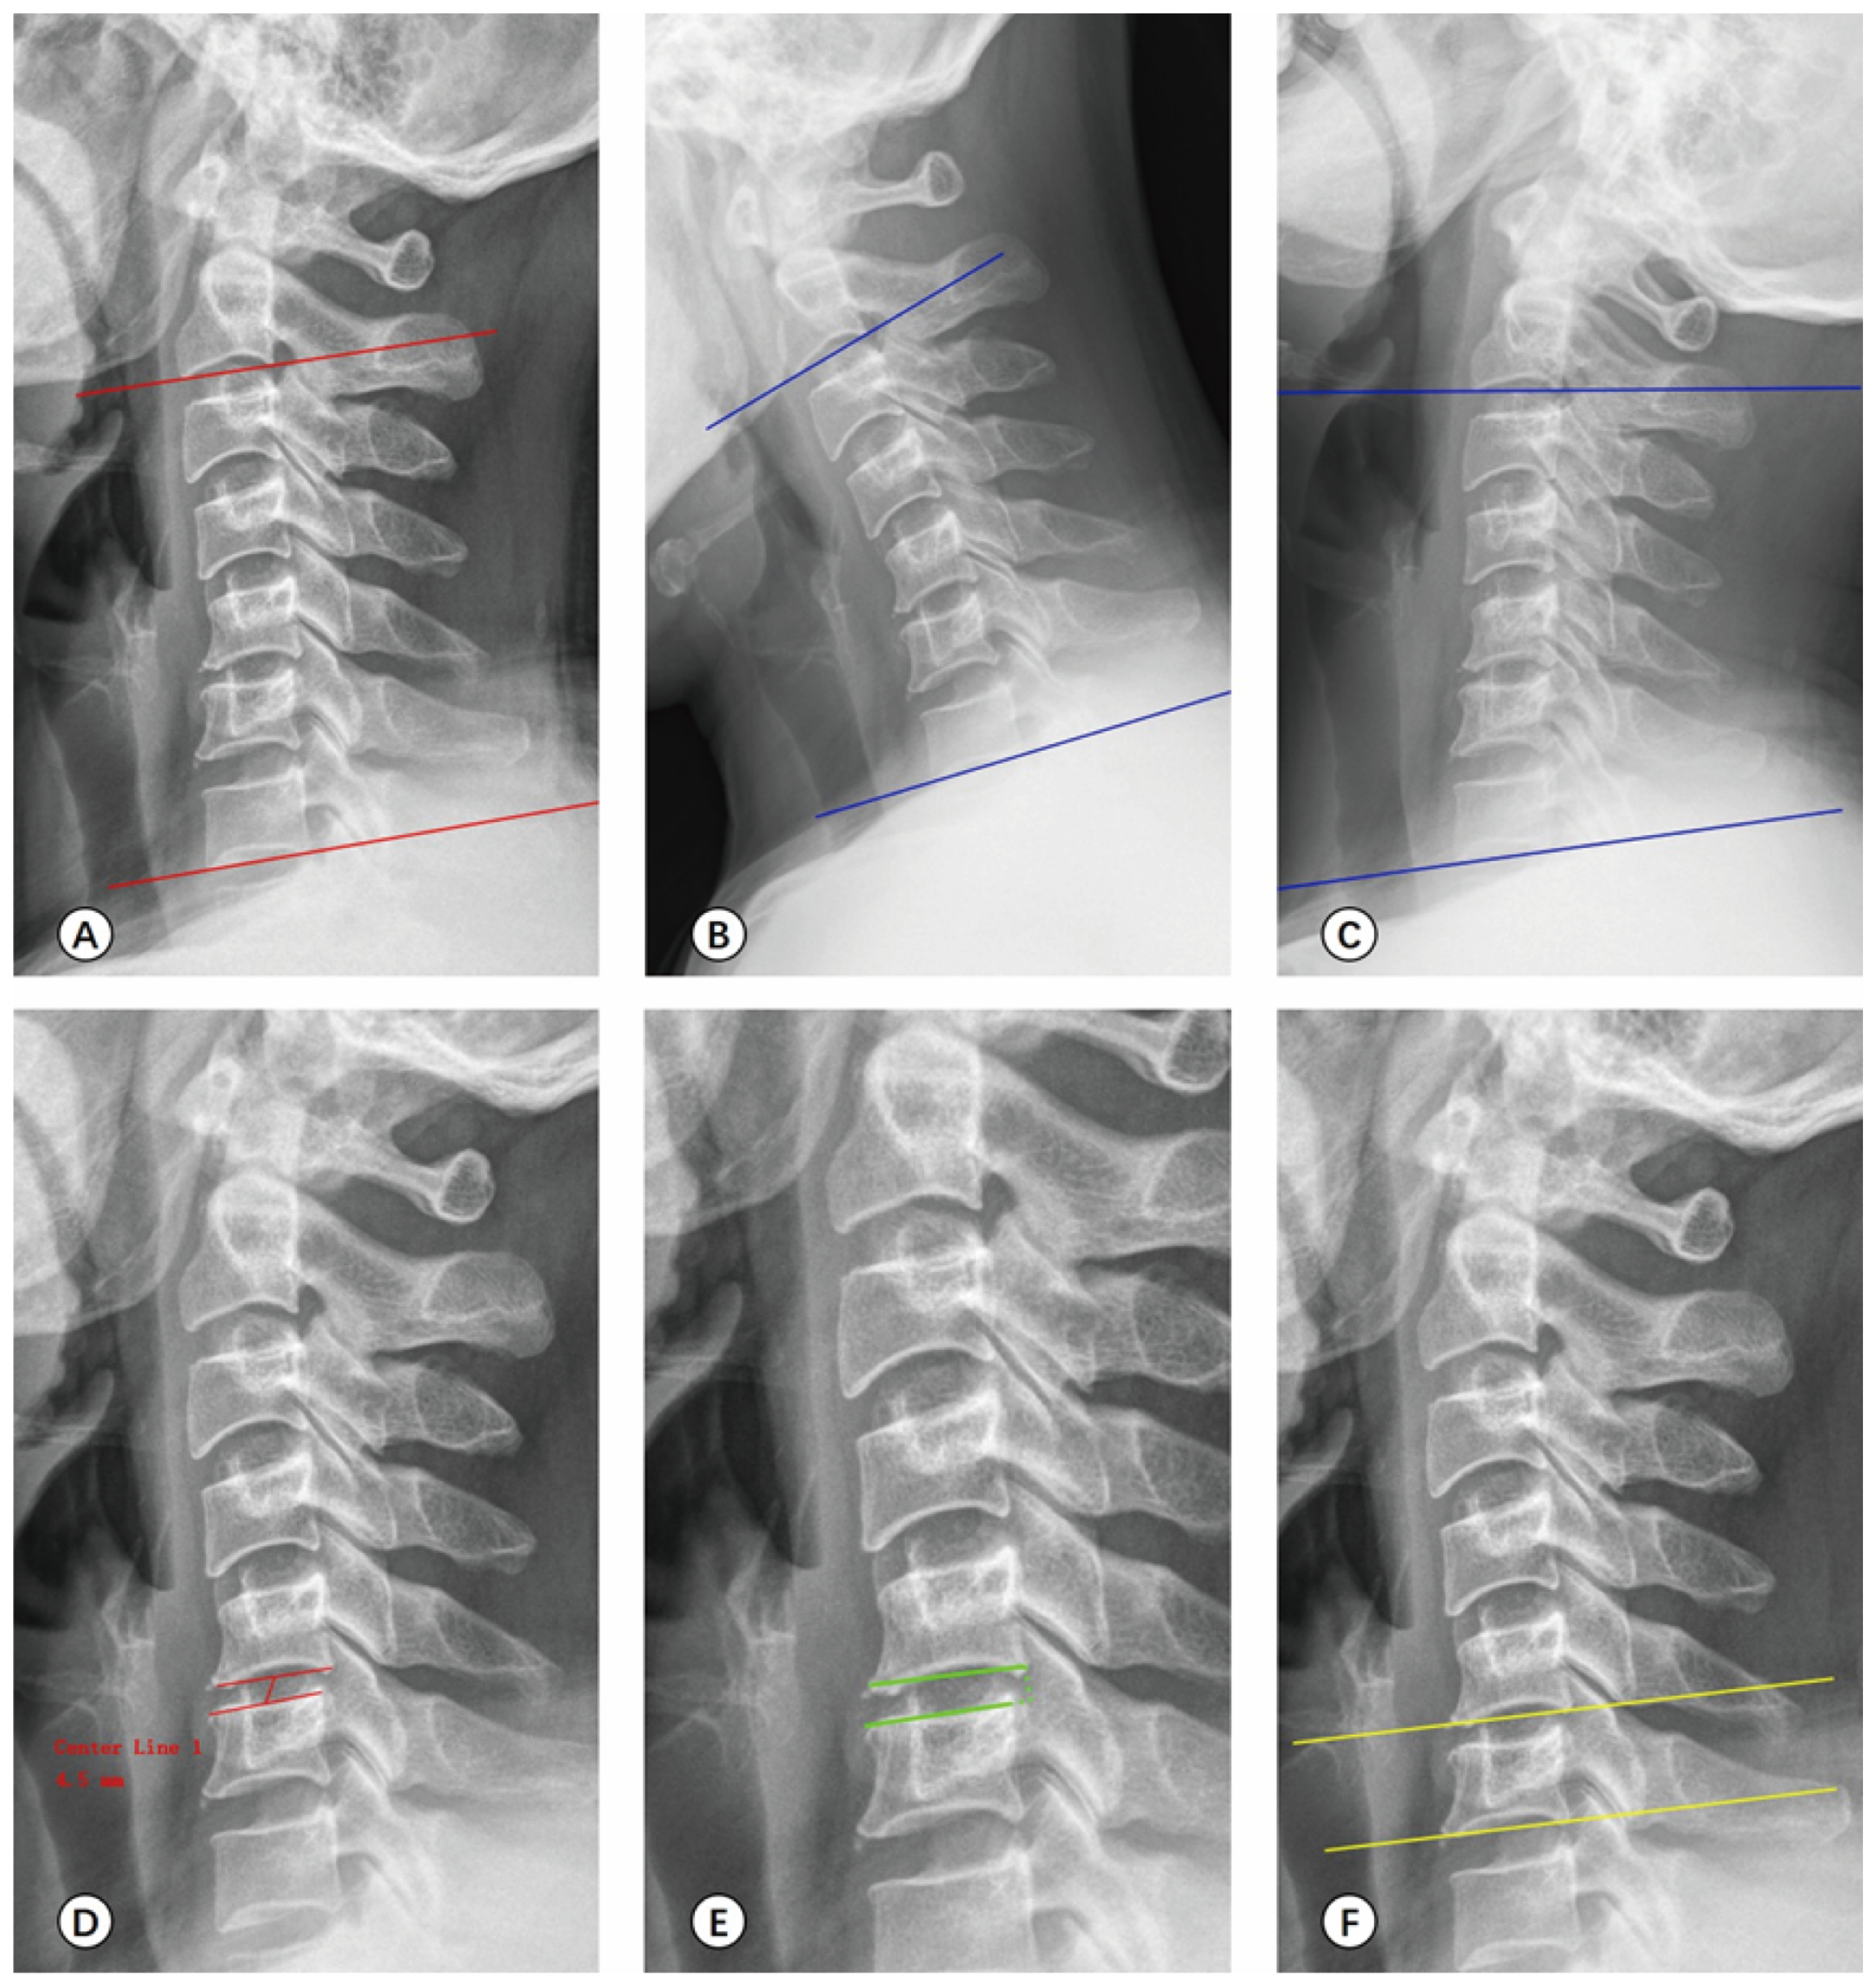

2.4.2. Radiological Measurement

| Before | 12 Months After Surgery | Last Follow-Up | F | p | |

| C2-7 Cobb’s angle (°) | |||||

| UBE | 16.87 ± 2.89 *,† | 23.41 ± 4.04 * | 24.46 ± 3.94 † | 97.527 | <0.001 |

| PE | 16.66 ± 2.70 *,† | 22.38 ± 5.73 * | 23.53 ± 6.02 † | 39.525 | <0.001 |

| C2-7 ROM (°) | |||||

| UBE | 22.60 ± 7.59 *,† | 24.58 ± 9.58 *,‡ | 27.57 ± 9.45 †,‡ | 6.997 | 0.001 |

| PE | 22.08 ± 8.23 *,† | 25.71 ± 8.17 * | 26.42 ± 9.62 † | 4.500 | 0.013 |